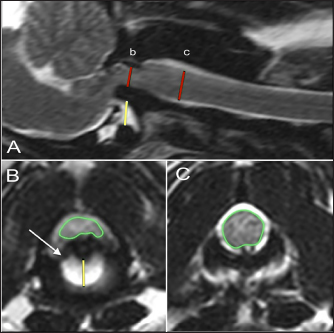

Fig. 4. T-2 weighted sagittal images of three dogs affected by an atlanto-axial subluxation in this study (TE, 120 ms; TR, 3800 ms; slice thickness, 2.5 mm). (A) This dog with atlantoaxial subluxation has intramedullary T2 hyperintensity at the level of compression that likely indicates edema or ischemia (red arrow). Chiari malformation is absent. (B) There is Chiari malformation causing impaction of the cerebellum, with similar intramedullary hyperintensity at the level of compression as in A (red arrow) but additional pre-syrinx formation caudal to the level of spinal cord compression (yellow arrow). This dog was also graded as having moderate hydrocephalus. (C) There is Chiari malformation causing indentation of the cerebellum and focal syringomyelia greater than 2 mm in diameter.